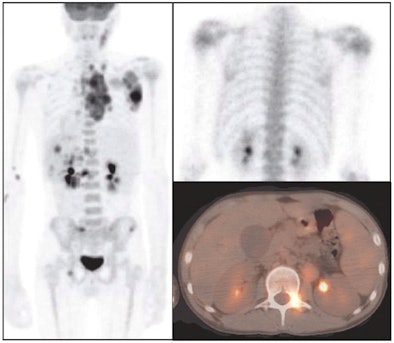

| Images of a 14-year-old boy with nodular sclerosing Hodgkin's lymphoma at presentation. The left panel shows a posterior projection image from an FDG-PET/CT scan with many areas of abnormal osseous and nonosseous uptake, in particular L2, right iliac crest, and left inferior acetabulum. The top right panel is a bone scan posterior planar view of the chest and upper abdomen, which shows only equivocal, minimally elevated uptake in the left aspect of L2. The bottom panel is a transverse fusion PET/CT image, which localizes the abnormal uptake in L2 to the left posterior elements. Images courtesy of St. Jude Children's Research Hospital and Dr. Barry Shulkin. |